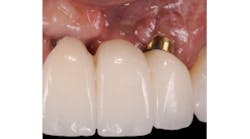

Figure 1: Patient reported discomfort and periodic fistula on labial mucosa of Nos. 10/22. Existing bridge is 12 years old, with implant Nos. 9/21 submerged. Previous history of failed implants/GBR in same area. Buccal plate regeneration was achieved with SMART bone graft. Stable bone volume and no symptoms after two years.

Anorganic bovine bone xenograft particles are mixed with recombinant human platelet-derived growth factor (rhPDGF-BB). The combination is delivered into the subperiosteal pouch with a specially configured carrier and compacted. No marrow penetration, space-making devices, or membranes are required. Particle aggregation within the pouch results in horizontal bone augmentation lateral to the exposed implant surface (figure 1).